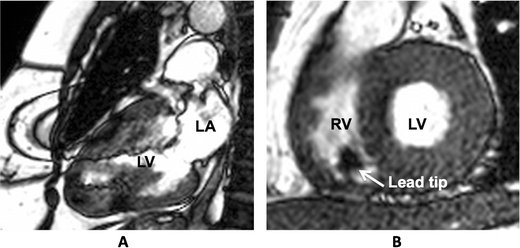

Current clinical trials

An overview of clinical trials currently enrolling patients is given in Table 2. Apart from demonstrating the safety of a device in an MRI environment, contemporary studies are more focused on the influence on image quality and artefacts caused by the CIED (Fig. 1).

Fig. 1

Steady state free precession CINE images. Typical artefacts as can be observed in patients with an implanted impulse generator (a) and pacing leads (b). Note that the image quality in the short axis cine (b) is sufficient to allow reliable calculation of left ventricular ejection fraction